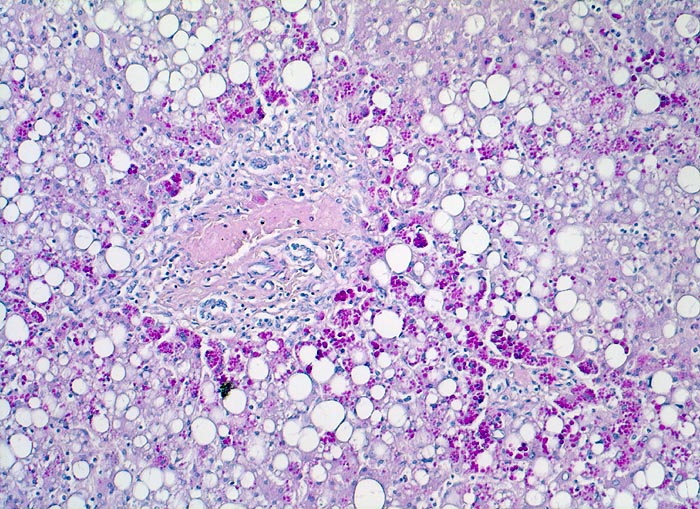

alpha-1-Antitrypsinmangel

Diastase-PAS positive Einschlüsse von alpha-1 Antitrypsin in periportalen Hepatozyten.

Bei Patienten mit alpha-1 Antitrypsinmangel wird das alpha-1 Antitrypsin nicht ins Blut abgegeben, sondern in Hepatozyten gespeichert, wo es zu einer Entzündung und Fibrose der Leber führt. Alpha-1 Antitrypsin schützt die Lunge vor Abbau durch Proteasen. Deshalb entwickeln Patienten mit alpha-1 Antitrypsinmangel ein Lungenemphysem.